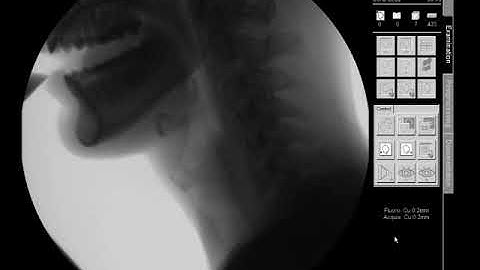

Normal Swallow Tutorial with Modified Barium Swallow